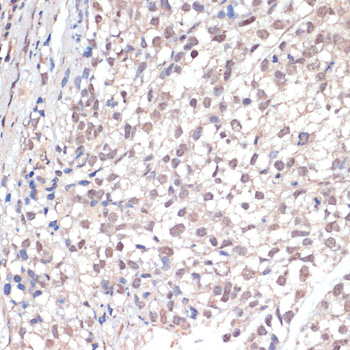

Immunohistochemistry of paraffin-embedded human gastric cancer using c-Jun antibody at dilution of 1:100 .